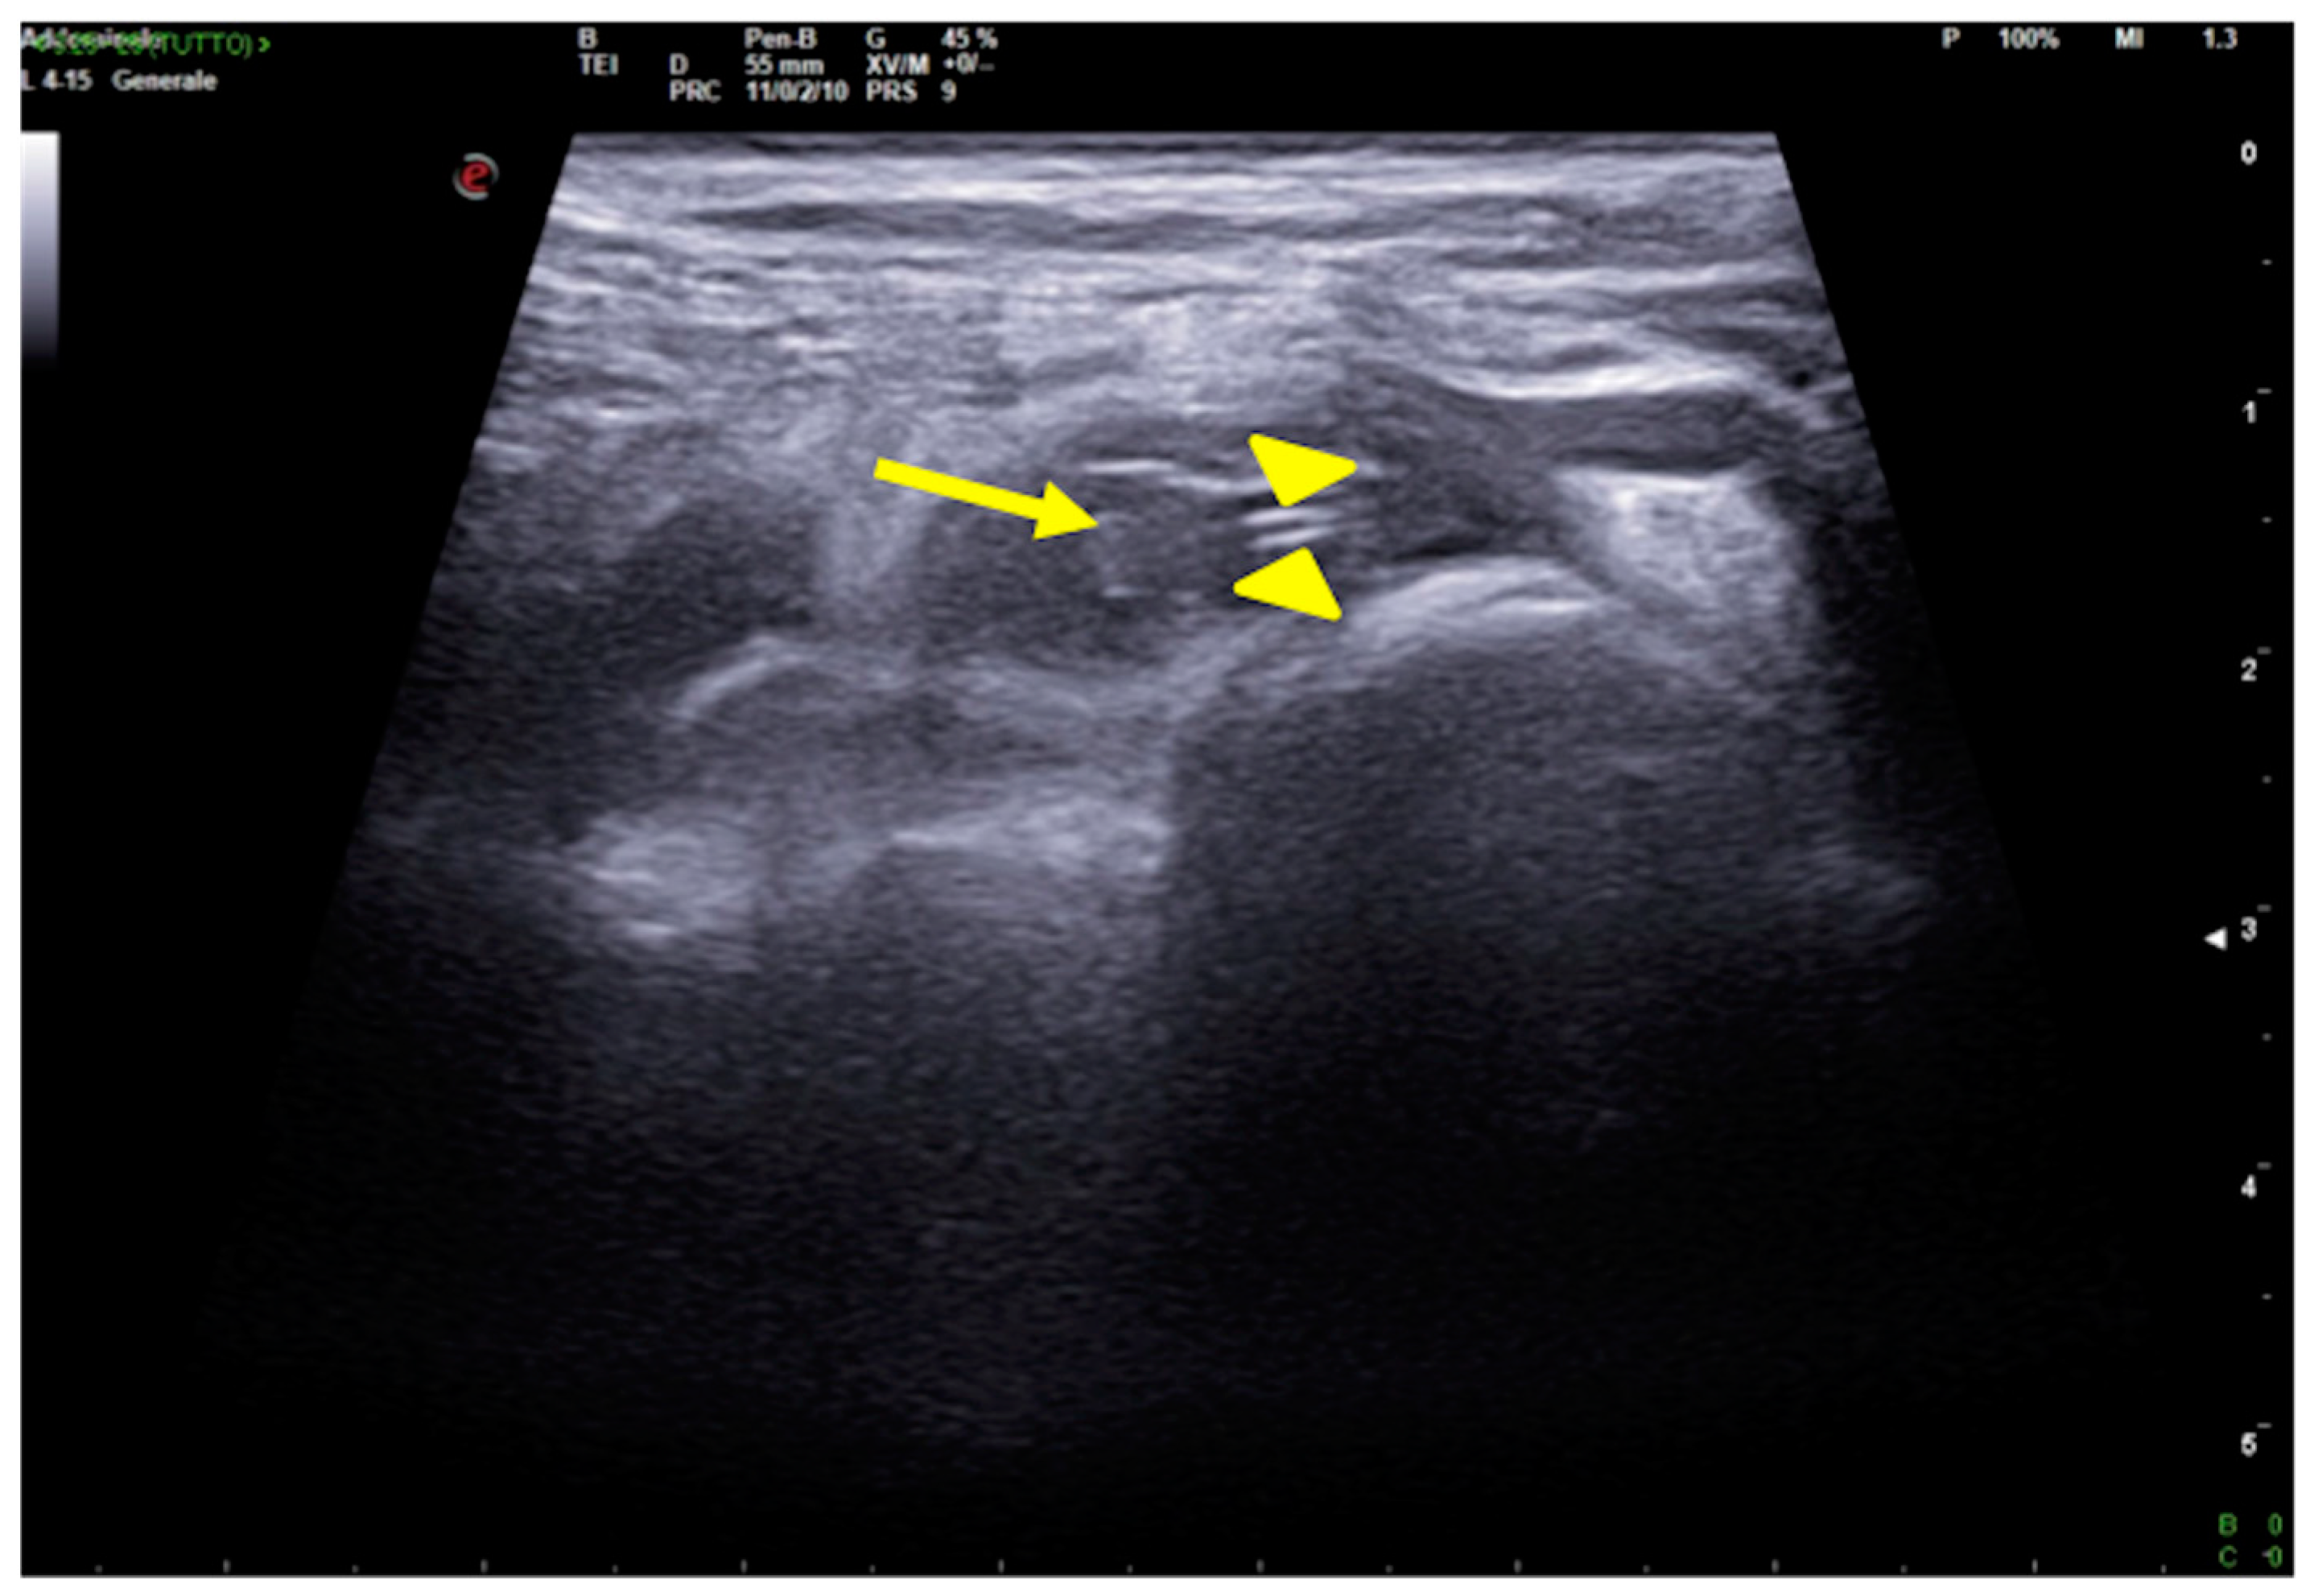

3. Confirming or Excluding Pneumothorax and Monitoring its Evolution